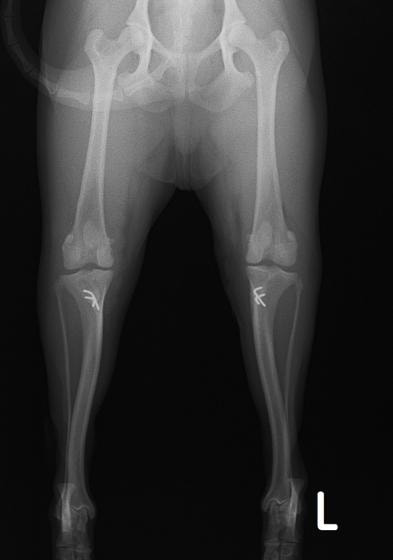

■ 症例24 キャバリア 7か月

左右膝蓋骨内方脱臼(左:グレードⅣ 右:グレードⅢ)

以前から左右後肢の跛行が認められ、整形外科学的検査・レントゲン検査により左右の膝蓋骨脱臼が認められた。症状が重度である左膝の膝蓋骨脱臼整復術を行った。外科手技は縫工筋及び内側広筋の解放、脛骨粗面の外側転位、滑車ブロック形造溝術、内外側関節方の縫縮を実施した。術後一か月時点で、左の膝蓋骨は安定しており経過は良好である。

本症例は成長期における重度の膝蓋骨脱臼であり、術後の再発の可能性もあるため、経過をしっかりと観察していく必要がある。また、今回手術を実施していない右膝に関しても経過を観察し、手術を検討していくこととする。